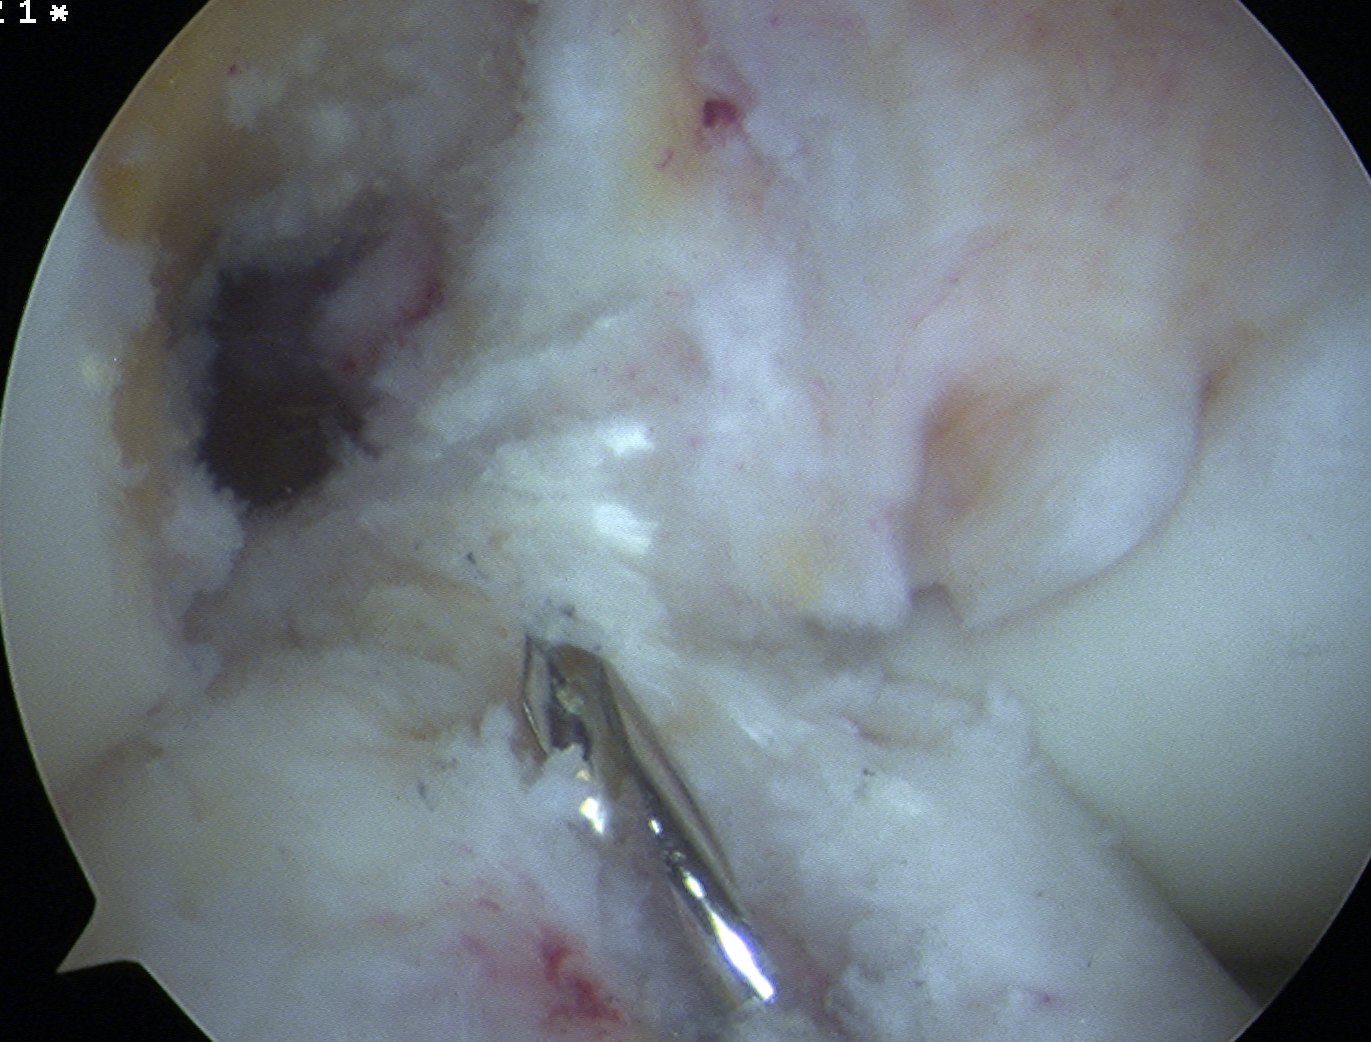

Prepare LFC

- notchplasty often required

- graft is significantly larger than HS